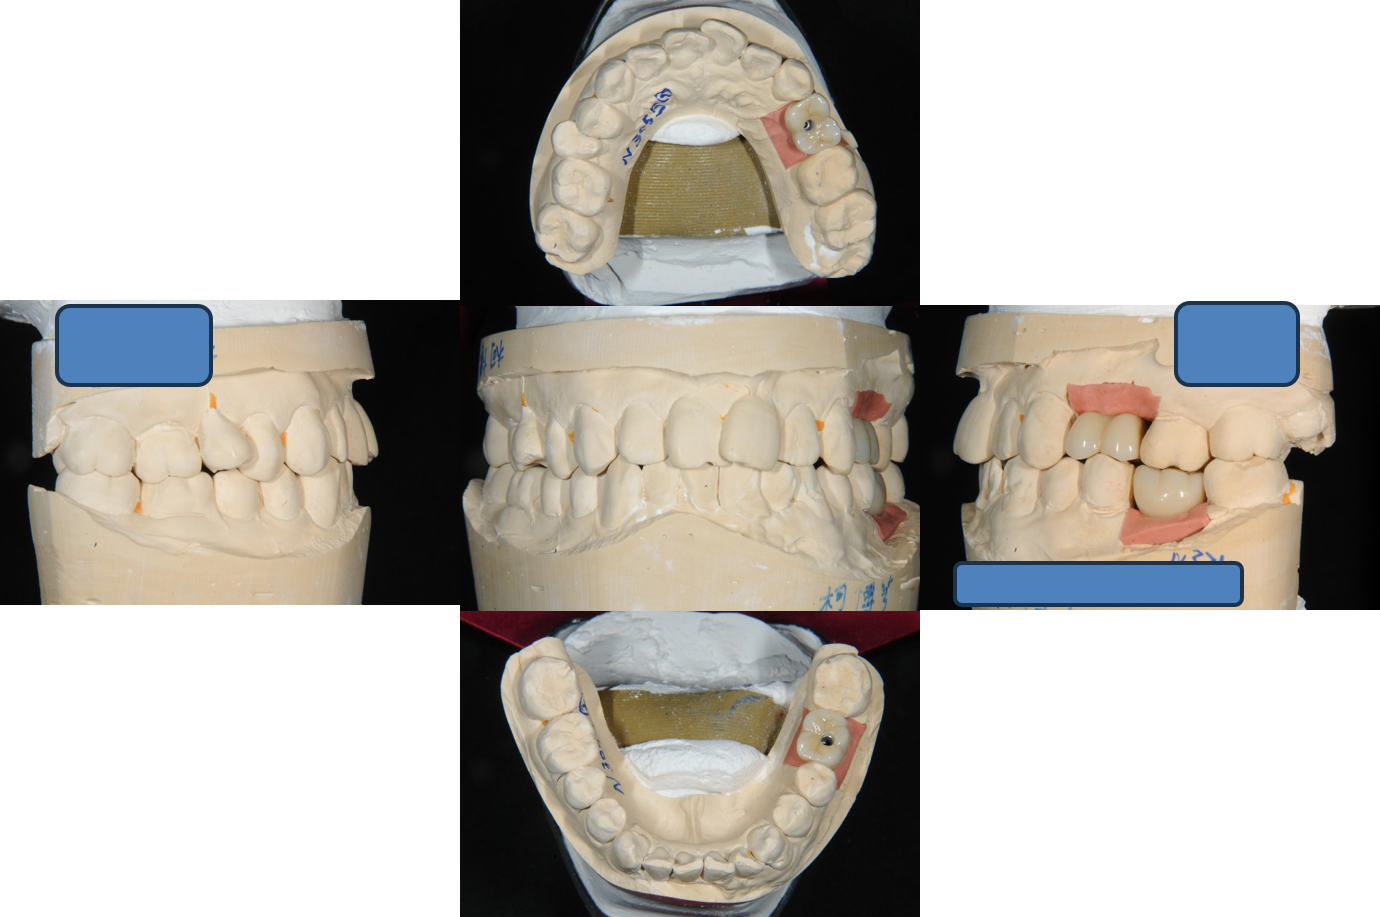

模型上咬合器

植牙印模與上咬合器